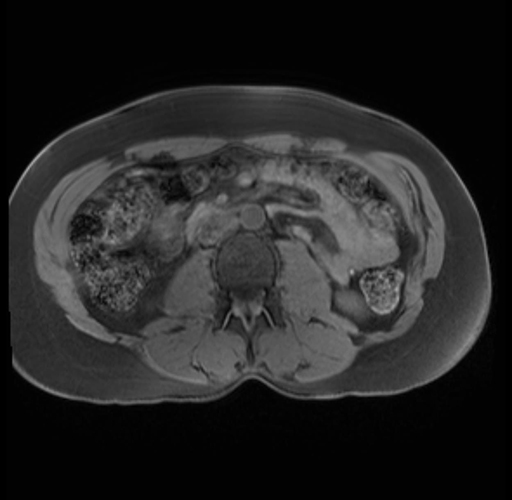

Imaging Analysis

Look through the patient's CT scan to identify any areas of concern for the necessary procedure.

Based on your CT findings, which issue(s) are present and would give reason for "planned slowing down moment(s)" in this case?

Considering a standard distal pancreatectomy procedure, what step(s) of the operation would you do differently in this case?